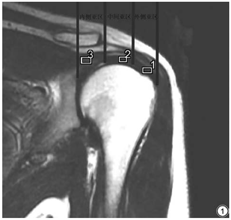

扫描完成后由2名具有10年以上骨肌系统疾病诊断经验的放射科医师独立阅片,采用盲法评价图像并纳入肌腱炎病例,意见不同时经协商达成一致。另外使用GE主机MAGiC处理软件包进行图像后处理,生成T1 mapping、T2 mapping 和PD mapping 3组定量图谱。于Magic序列生成的T2WI斜冠状位图像上将冈上肌肌腱分为外侧亚区(指冈上肌肌腱纤维远侧插入部位)、中间亚区(指外侧部位和内侧部位连线的中点部位)及内侧亚区(指位于外侧部位内侧方向2 cm左右、高于肱骨头软骨的区域)[17],如图1所示。根据肌腱的走形分别于3个亚区勾画感兴趣区(region of interest, ROI),勾画时避开脂肪及周围其他组织,ROI的勾画及测量分别由前2名放射科医师(观察者1和2)独立完成,并在间隔至少2周后重复测量数据,以评估观察者间和观察者内的一致性,最终的分析数据为2名医师4次测量结果的平均值。